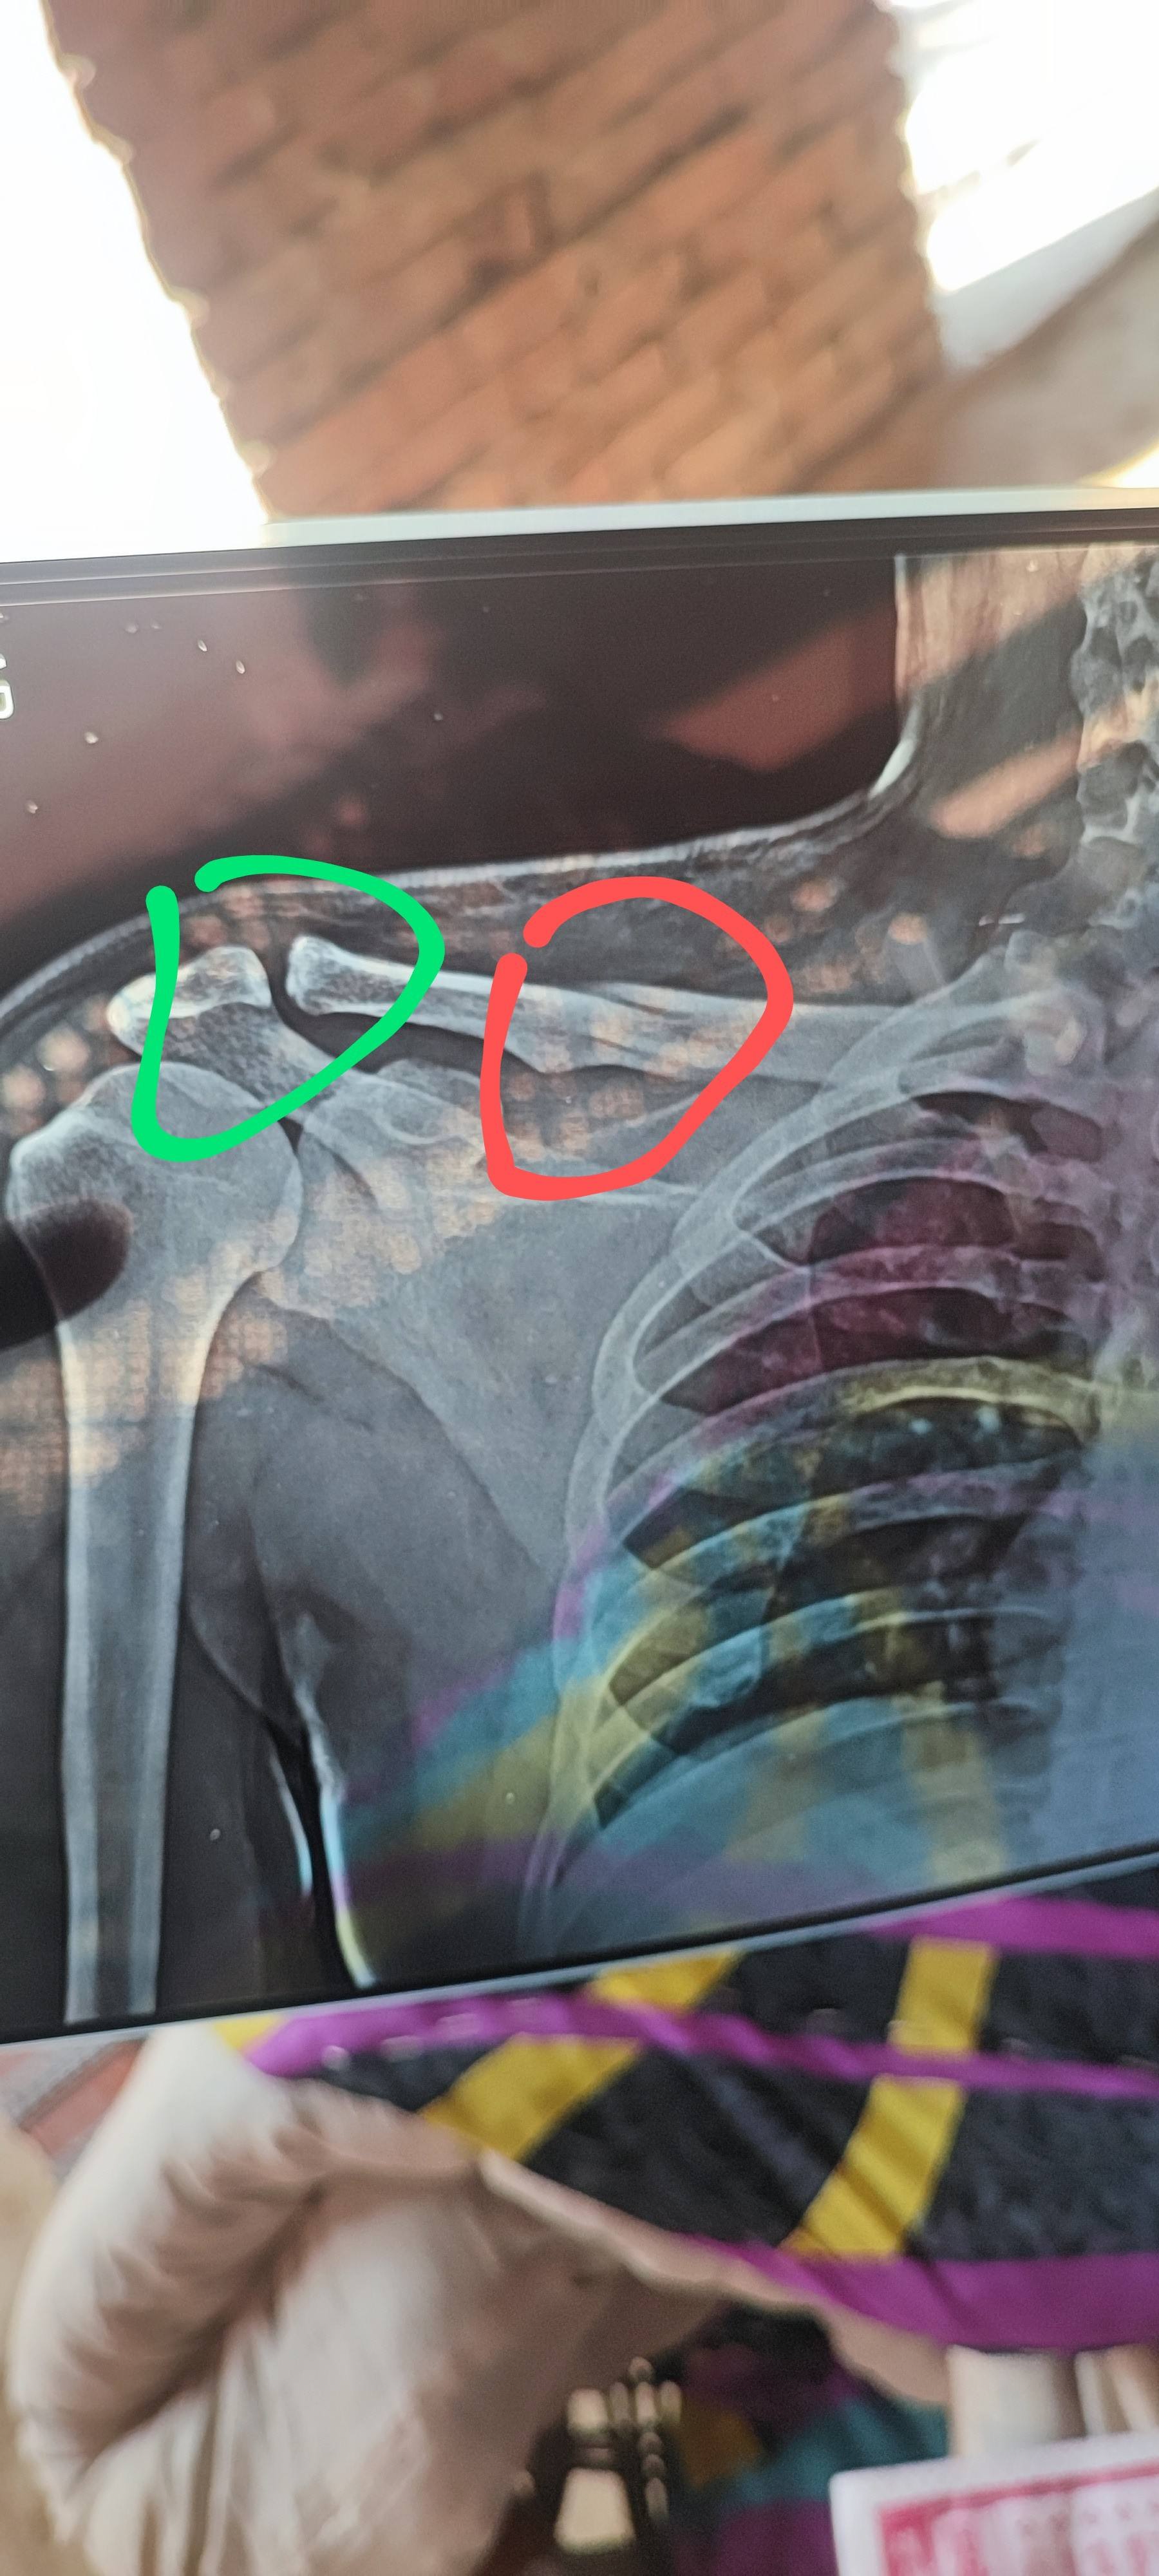

Clavicle bone fracture